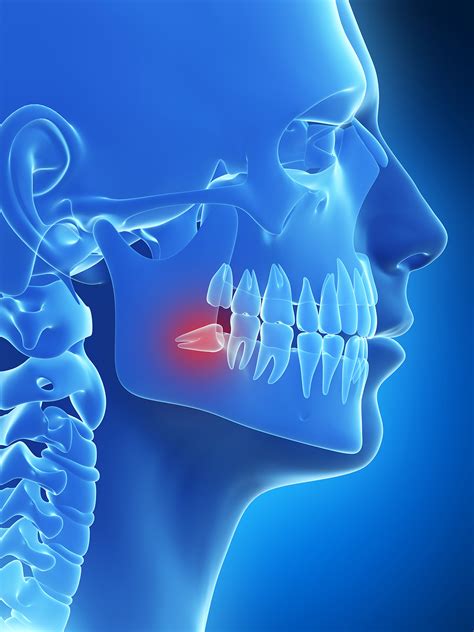

The Anatomy of Wisdom Tooth Development

Not everyone has room for these teeth. In fact, evolutionary changes have resulted in many modern humans having smaller jaws that simply cannot accommodate four extra molars. When there isn’t enough space, the tooth may become impacted. An impacted tooth is one that is blocked from fully erupting by neighboring teeth or bone. This can lead to complications such as infection, cysts, or damage to the adjacent second molars.